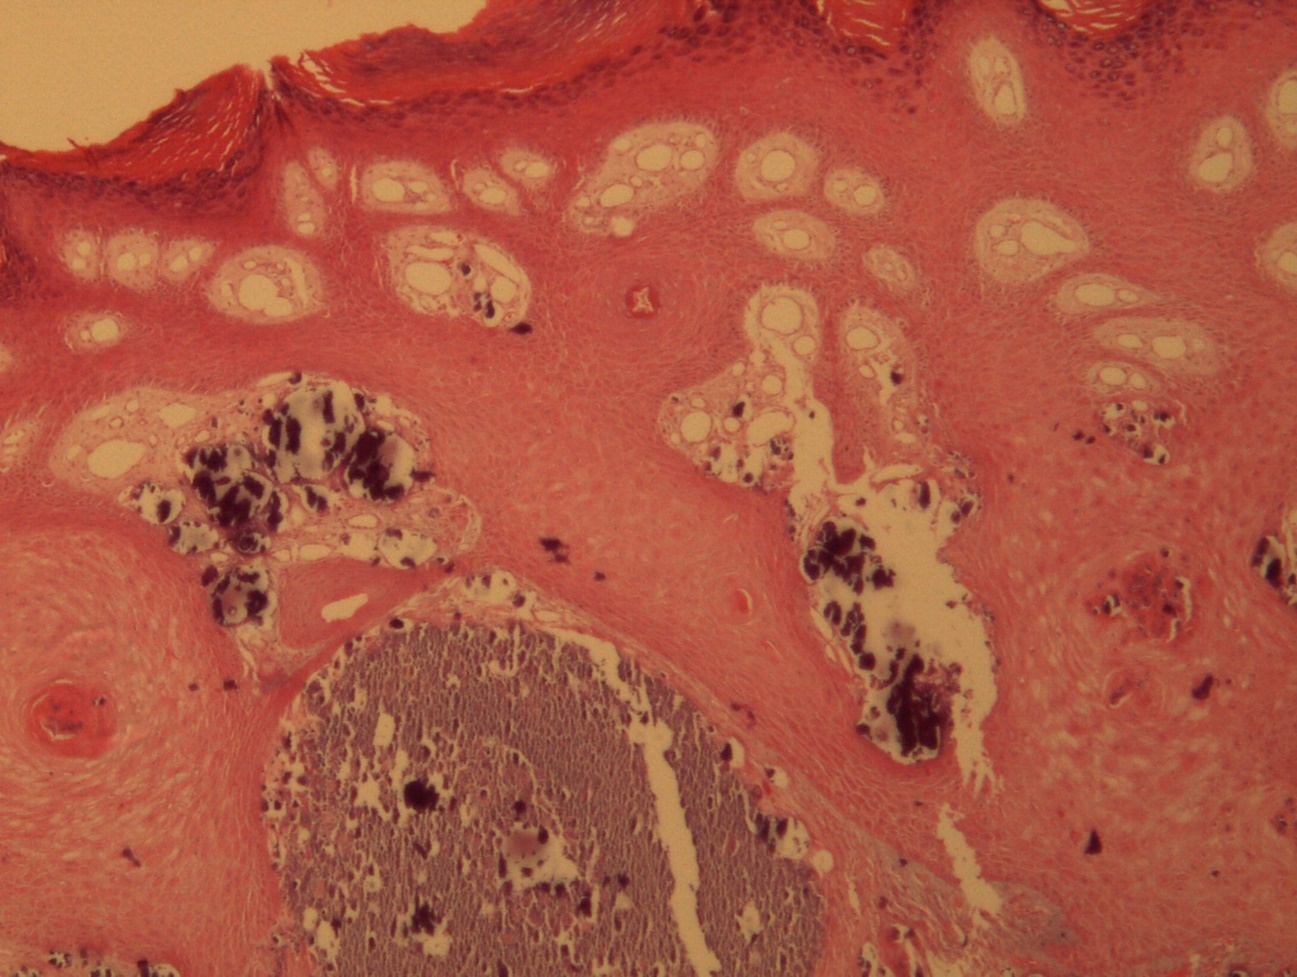

A 9-year-old male patient who was treated in the dermatology service for a progressively growing keratotic nummular dermal lesion on the right knee. With the clinical judgment of viral wart, the lesion was removed. In the Pathology Service, a nummular keratotic lesion of 0.5 cm in maximum dimensions was received, which crackled when cut. Figure 1, Figure 2, Figure 3, Figure 4, Figure 5

Figure 2.Common wart with calcium foci at the level of the dermal vessels grouped in lobules. HE. 200x.

Common wart with calcium foci at the level of the dermal vessels grouped in lobules. HE. 200x.